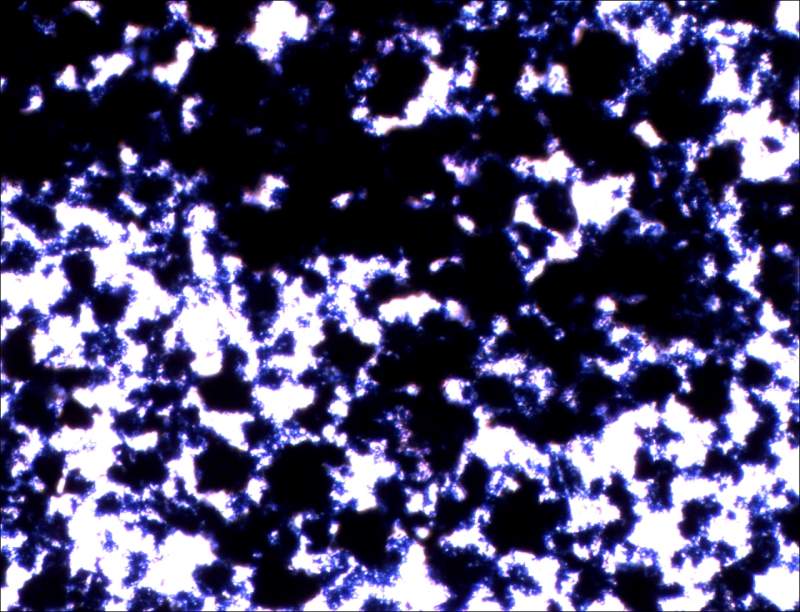

| 我用MTT法测药物对大鼠肝星状细胞的抑制作用,但预期结果完全跟预期的相反,给药组的OD值都比对照组高,已经三轮了,结果都是一样的,也没污染,种板也算均匀,这是为什么呢?求各位前辈指导啊 ! |